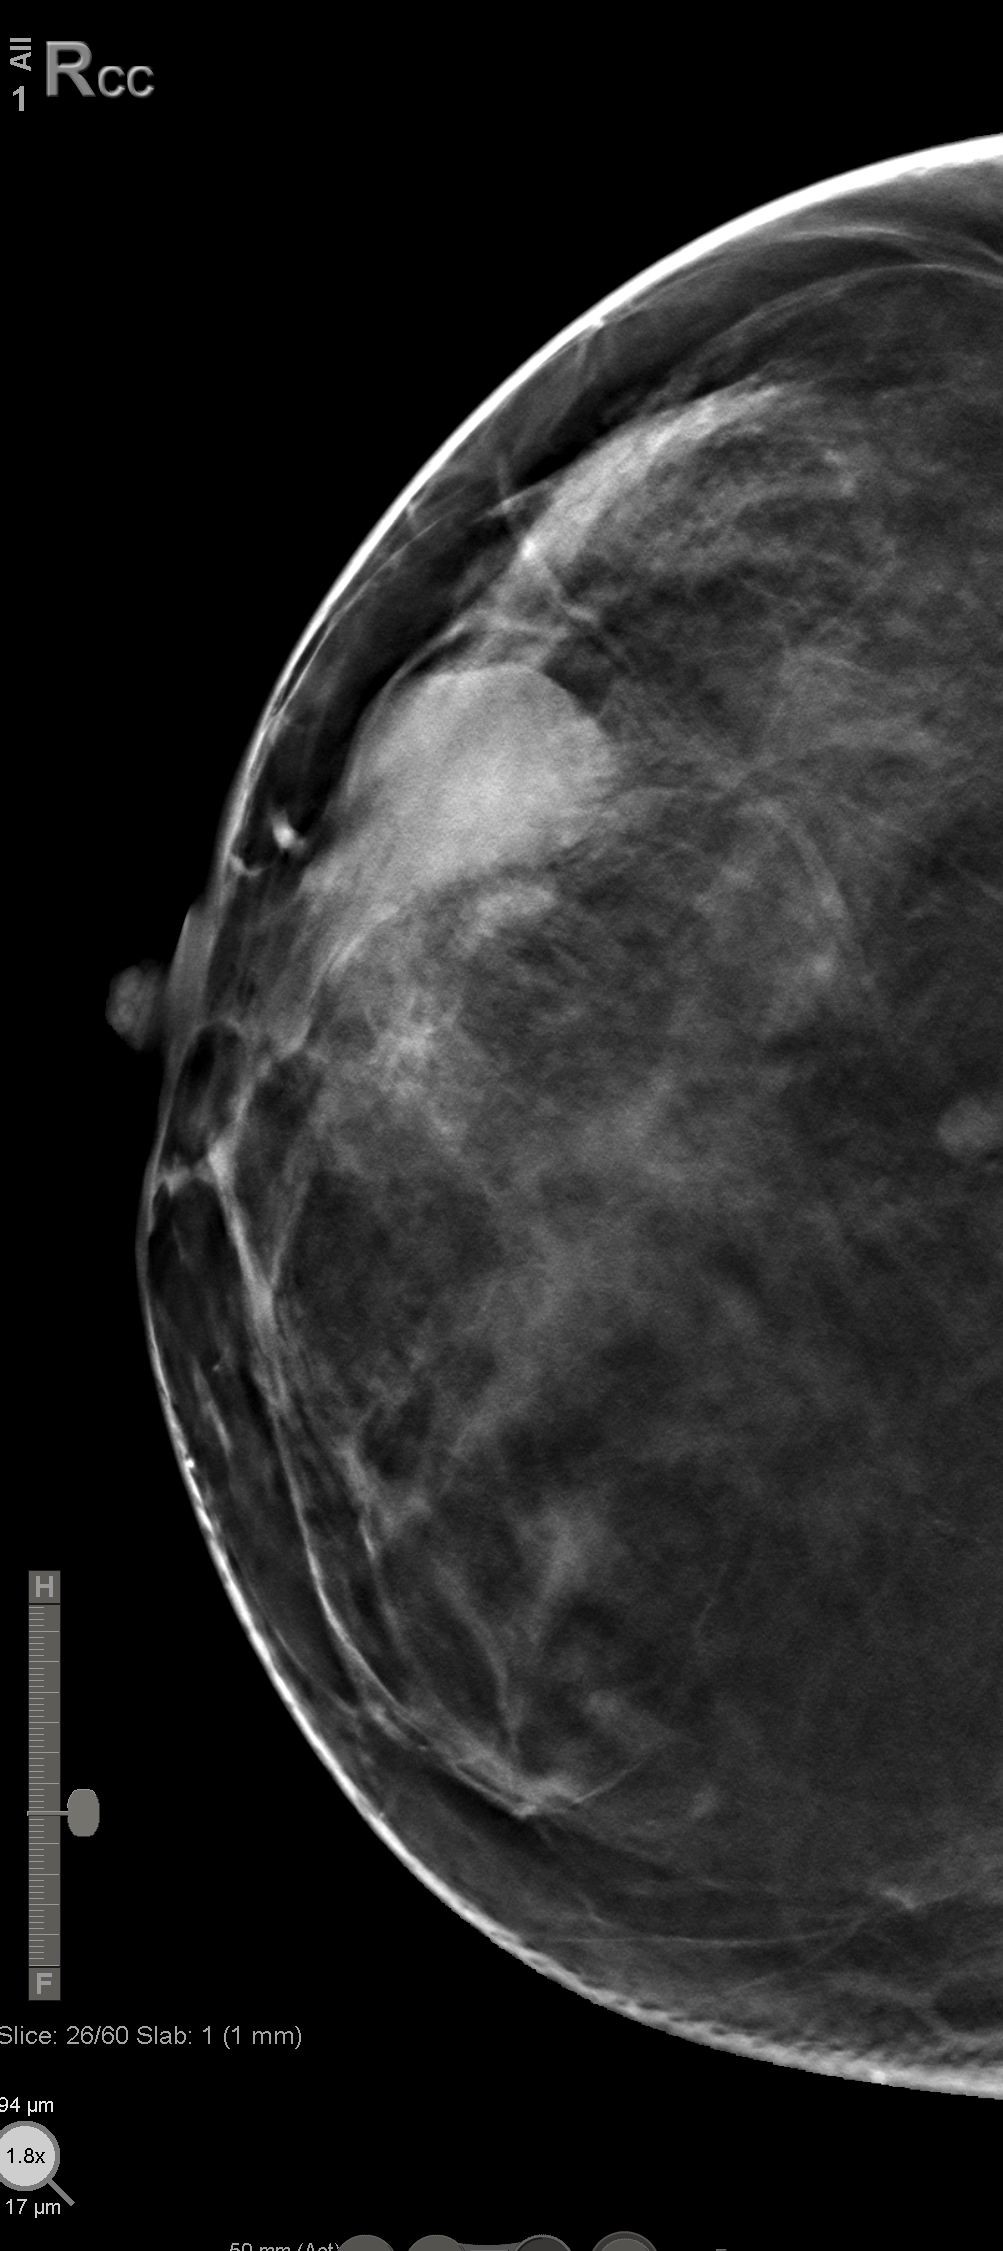

Bilateral Digital mammography , Craniocaudal (CC) and Mediolateral oblique (MLO) view with tomosynthesis images revealed a round shaped, equal density mass with indistinct margin in lower outer quadrant. No suspicious microcalcifications was seen. No significant axillary lymph nodes were present. A high resolution ultrasound of the right breast showed a round shaped, heterogeneously hypoechoic mass with irregular margin, small cystic spaces within and posterior acoustic enhancement, measuring about 1.6x1.9x1.5cm at 7 O’clock position. Mild internal vascularity was noted on colour doppler images. Right axilla showed suspicious lymph nodes with loss of fatty hilum and thickened cortex.